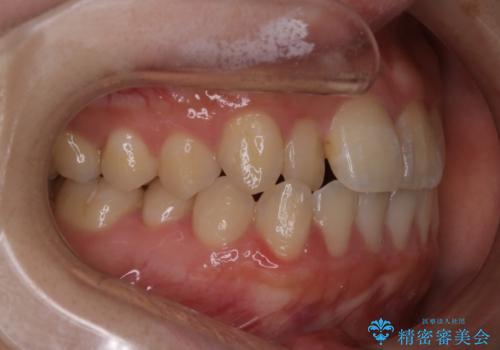

【インビザライン】前歯のがたつきを目立たない装置で治療

- 前歯の叢生を主訴に来院されました。目立たない装置を希望されたためインビザラインで治療を行いました。

IPRと拡大をし、叢生を治しました。右上2番は反対咬合でしたが短期間できれいに治りました。